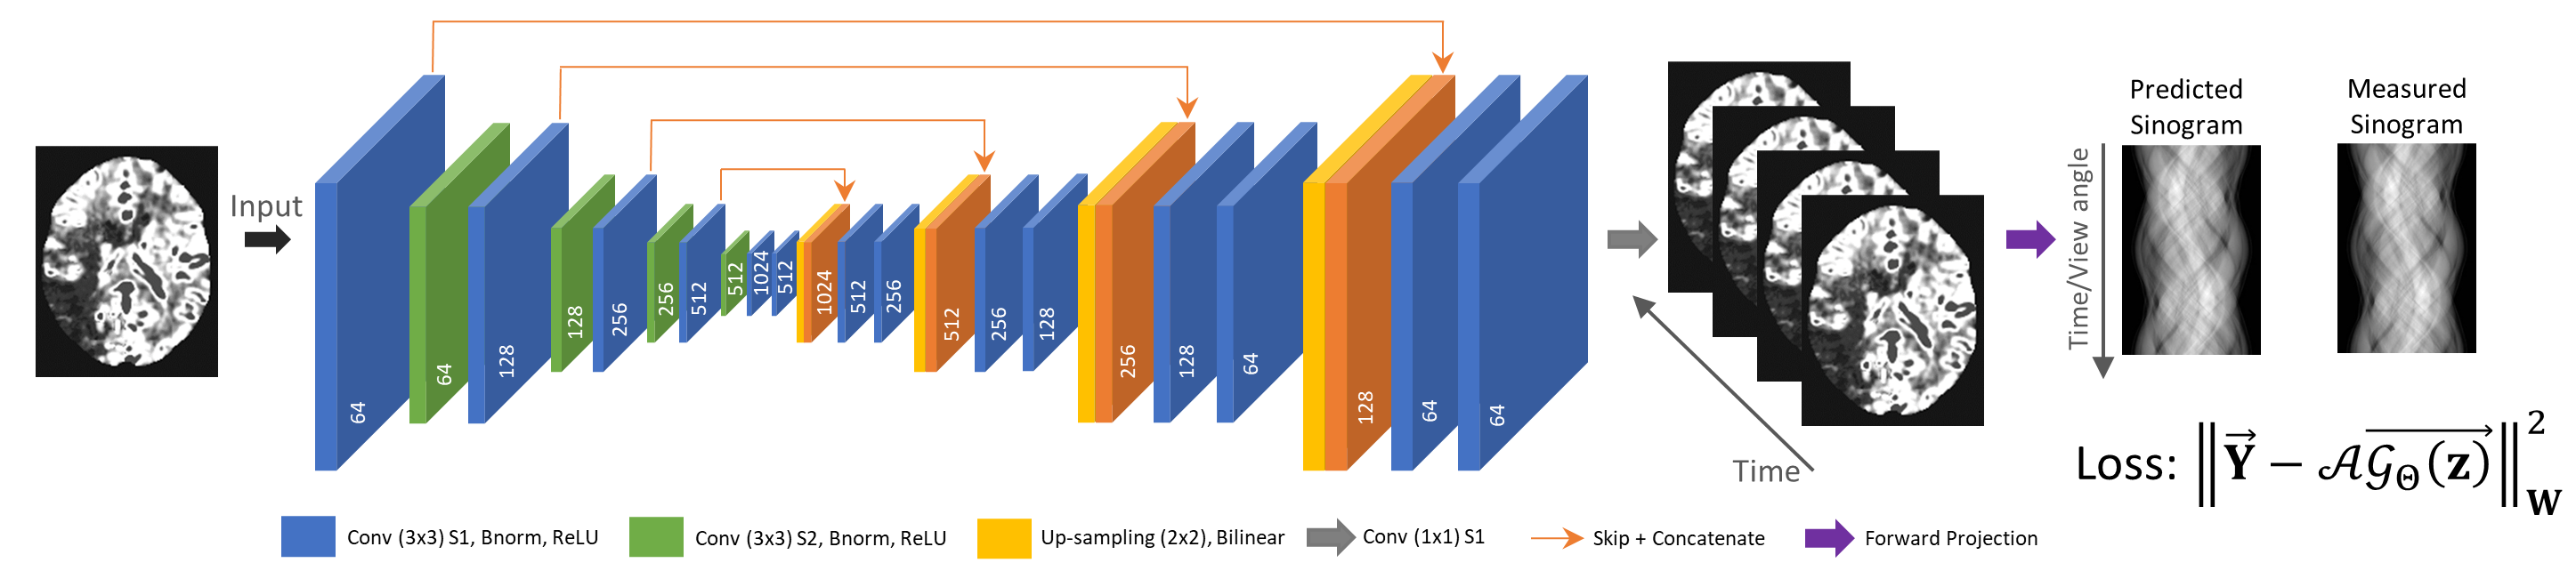

在CT数据采集过程中,被扫物体的动态信息被顺序地记录在每个视角投影数据中。获取单个视角投影数据所需时间很短,时间分辨很高,例如诊断CT的0.1毫秒或C臂锥束CT的25毫秒。我们很自然地想到使用单个视角投影数据约束上述沿时间维度外插过程。通过最小化外插图像序列和测量投影数据间的不一致性,得到最优的外插规则。

为实现上述想法,本文提出数据一致性约束的深度时间维度外插方法,利用数据一致性约束学习最优外插规则以提高时间分辨(如图2所示)。提出方法的创新性在于:(1)该方法将CT时间分辨提高至系统极限(即获取单个视角投影数据所需的时间---诊断CT的0.1毫秒或C臂锥束CT的25毫秒),从而同时最小化时间平均误差和数据不完备误差;(2)该方法适用于单个短扫描数据采集协议和非稀疏的成像任务;(3)该方法显式地使用每个患者测量投影数据,使得学到的外插规则对每个患者来说是最优的(如图3所示)。

图2. 方法流程图。